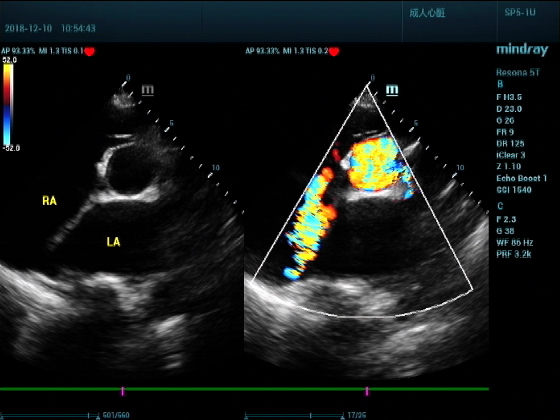

男,81岁,全身浮肿来住院

超声可见:左房,右房,右室明显增大,主肺动脉及右肺动脉增宽,二尖瓣中度反流,三尖瓣重度反流,肺动脉轻度高压,心律不齐

心包积液盆腔积液。淤血性肝增大,肝静脉增宽。(右心衰声像改变)